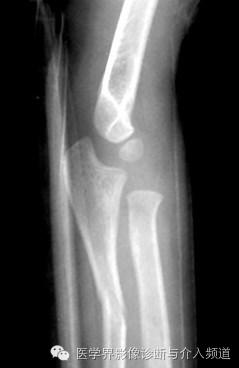

13、Monteggia 骨折

尺骨近端骨折并桡骨小头前脱位。多有外翻性暴力造成。